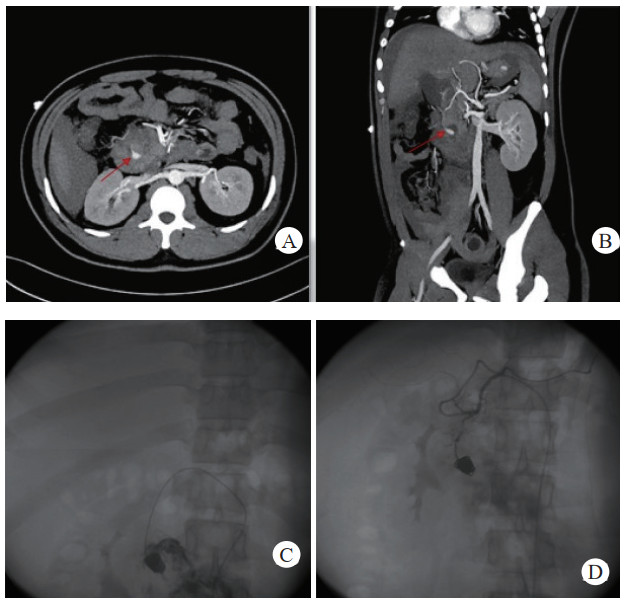

患者经介入栓塞治疗后,长期的随访CT及增强CT中,未出现责任动脉或瘤体再次发生破裂导致二次出血、弹簧圈移位及血栓异位栓塞等并发症,见图 3(病例3)。

| 注:A、B为患者术前CT增强扫描及血管重建技术,示胰腺炎影像,腹腔内见一血肿影,内可见与动脉强化一致的动脉瘤影像(箭头示),其供血动脉为胃左动脉;C为患者术后三天复查CT增强扫描,示血肿较前吸收减小,内见弹簧圈影及未见对比剂外溢。D为患者术后三年复查CT增强示,血肿消失,原动脉瘤处可见弹簧圈影及未见对比剂外溢 图 3 病例3术前、术后CT平扫及增强 |